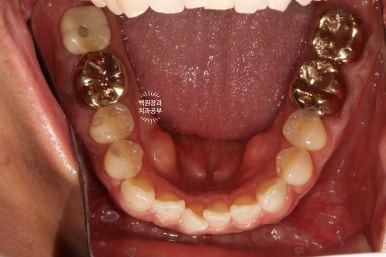

수술 후 약 3개월 정도 지난 후의 입 안 사진입니다.

다소 잇몸에 수술 자국은 있어보이나, 대체로 잘 아물어 있는 것을 볼 수 있었습니다.

다시 한 번 간단한 시술을 통해 임플란트 주변 뼈이식이 잘 유지되고 있는지를 확인합니다.

덴티움 뼈이식재와 차폐막은 오랫동안 형태를 유지하며 조화로운 치료 결과를 보여주네요.

아주 만족스러운 결과를 직접 눈으로 확인하고 치유지대주 (Healing abutment)를 연결해드렸습니다.

잘 보시면, 처음에 치료된 모습 그대로 잘 유지되고 있는 임플란트 크라운을 왼쪽에서 보실 수 있습니다.

충분히 단단한 지르코니아 크라운으로 제작된 임플란트는 오랜 수명을 자랑합니다!

그리고 오른쪽 사진에서, 아주 완벽하게 잘 유지되고 주변 잇몸과 조화로움을 자랑하는 임플란트를 보실 수 있을거에요. 얼핏 보면 자기 치아랑 헷갈릴 정도라니깐요..